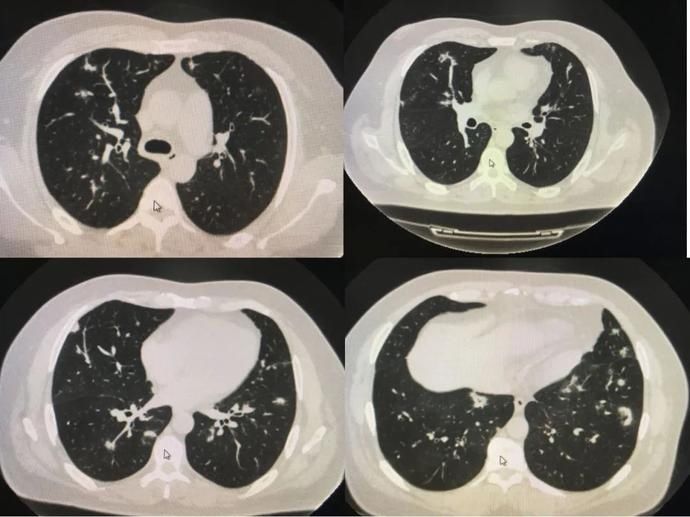

几乎70~80%做过胸部CT的人都会发现报告上写有「肺部小结节」,有的是单发小结节,更多的是多发小结节。尤其是高分辨薄层扫描CT,几乎让所有的小结节无从遁形。

影像学上≤3cm的球形或者类球形的病变都可以称为结节,其中<1cm的结节为小结节,<5mm的为微小结节。

在检出的肺部小结节中,绝大多数是良性结节,3mm以下的结节癌变可能性仅0.2%,直径≤6mm实性小结节绝大部分良性,恶性概率<1%。

有统计数据显示,低剂量螺旋CT查出的肺结节,96.4%是良性的。

在所有检出的肺结节人群中,真正考虑恶性结节并需要手术治疗的不足2%。

此外,相比较单发结节,多发结节恶性概率更低;相比较磨玻璃小结节,实性小结节良性可能性更大。